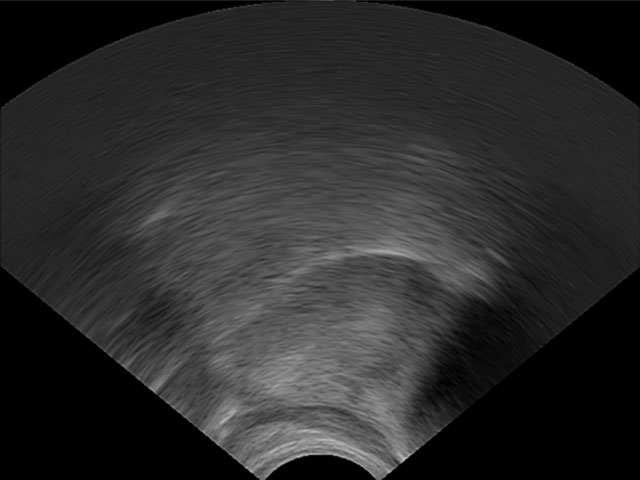

LinguaSound 3D, which is language independent, can simplify the interpretation of conventional ultrasound tongue imaging. A comparison of both imaging techniques is illustrated below for a normal English speaker:

| Conventional ultrasound tongue imaging | LinguaSound 3D | |

|---|---|---|

| Alveolar Stop /d/ | ![]() |

![]() |